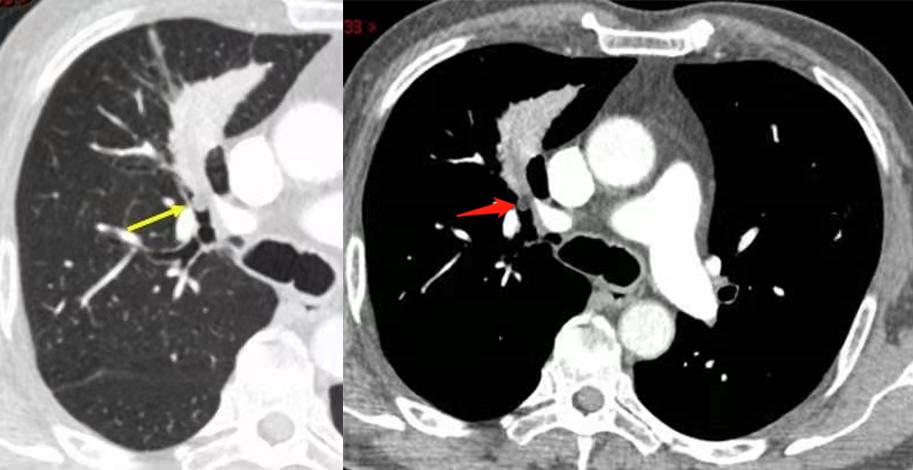

支气管腔内可见低密度结节,边界清晰,增强未见明显强化。